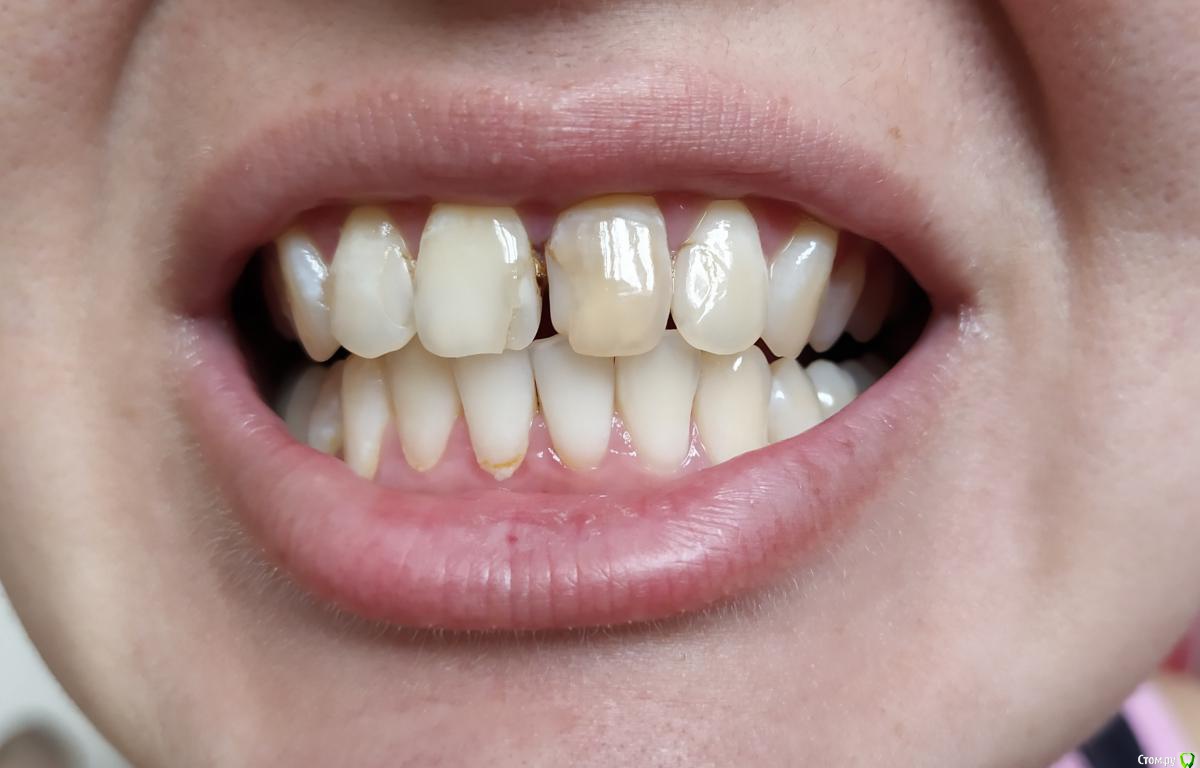

Реза Опубликовано 3 марта, 2020 Поделиться Опубликовано 3 марта, 2020 (изменено) Добрый день, очень нужна помощь, верхний левый зуб мертвый, между зубами большая пломба, также последующие 2 зуба с пломбой, для эстетики рекомендуют композит, хочу чтоб было надежно и долговечно, или все таки керамика лучше, посоветуйте пожалуйста Изменено 3 марта, 2020 пользователем Реза Ссылка на комментарий

Реза Опубликовано 3 марта, 2020 Автор Поделиться Опубликовано 3 марта, 2020 Фото прикрепила, посмотрите плизПосоветуем. Снимок выкладывайте искомой области. Можно фрагмент панорасного. Можно последовательные прицельные. Ссылка на комментарий

DmitrySH Опубликовано 6 марта, 2020 Поделиться Опубликовано 6 марта, 2020 Два варианта.1. Поправить пломбы на зубах 12.22, сделать винир на зуб 11 и коронку на зуб 212. коронку на зуб 21 и виниры 12,11,22 2 Ссылка на комментарий

Паращук Роман Опубликовано 11 марта, 2020 Поделиться Опубликовано 11 марта, 2020 композит на двойки,на правый центральный винир ,на левый коронка. Ссылка на комментарий